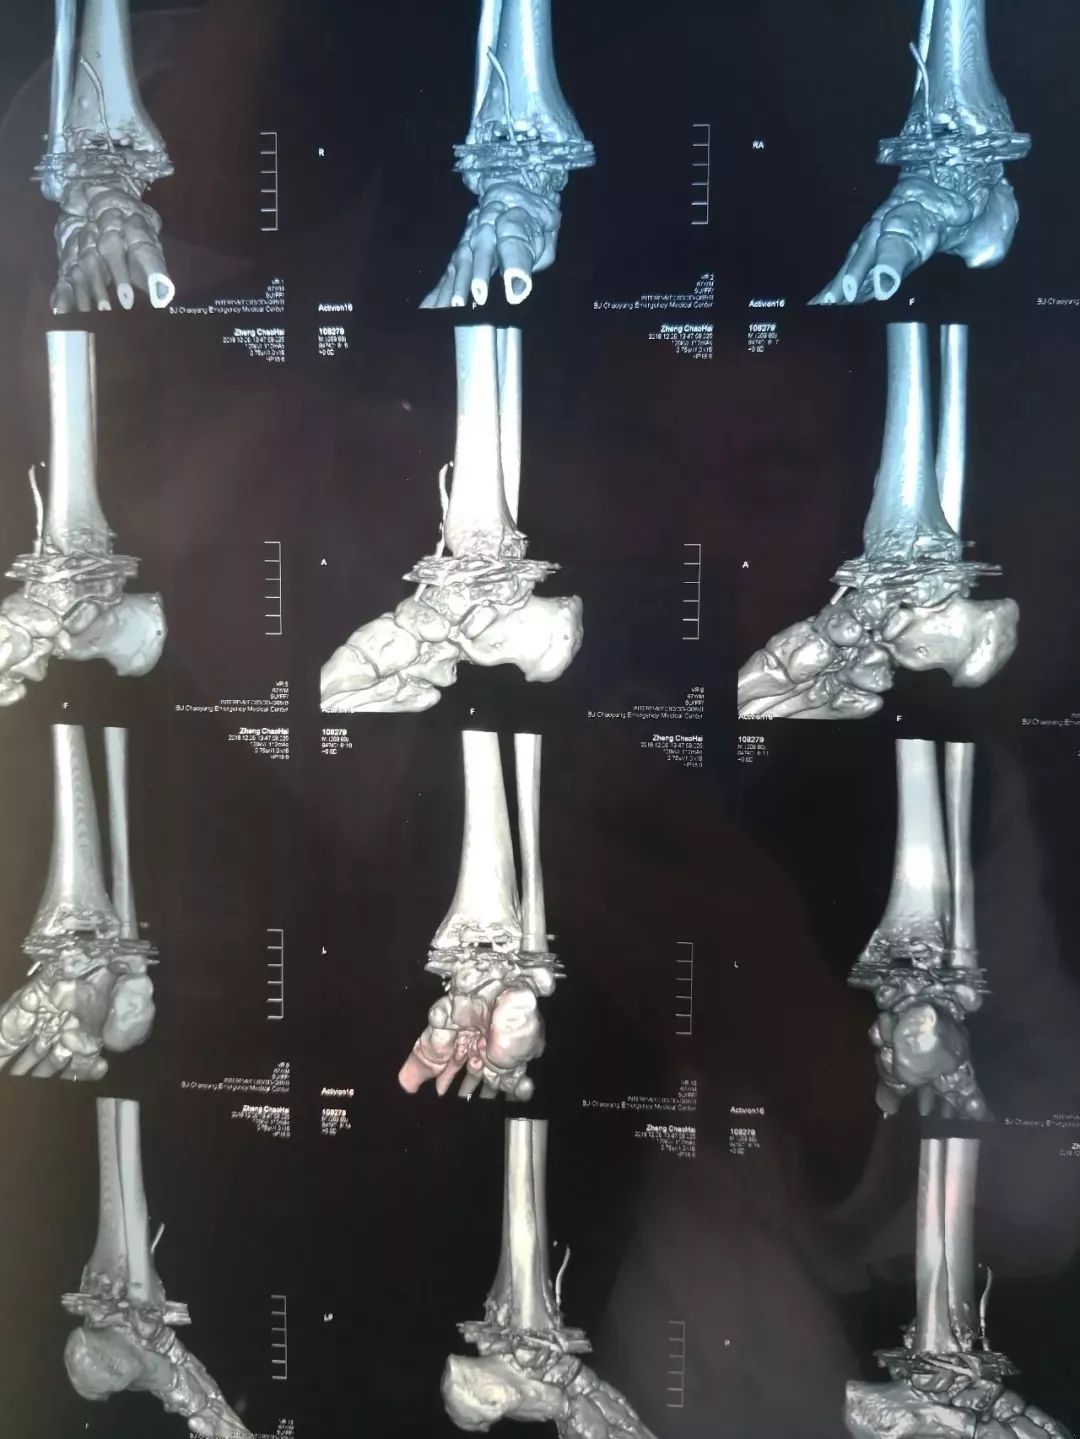

右踝关节胫腓骨远端及距骨,骨质不规则,部分骨质缺损,关节面边缘增生、硬化,多发高密度赘生物,关节间隙变窄。诊断:踝关节骨性关节炎。